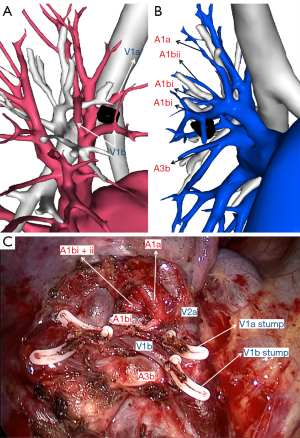

The pulmonary right upper lobe artery branching pattern of our case was superior trunk, inferior trunk, and an ascending artery. The superior trunk comprised A1 and A2a, while the inferior trunk comprised A3 and A1bii. We dissected 2 arteries, including A1bi and A3b. A1bi was located both anterior and posterior to B1bi, and A3b was located at the anterior side of B3b and shared a common trunk with A1bii and A3a (Figures 4,5).

The 3D reconstruction indicated the branching pattern of the pulmonary vein as an “anterior type”, V2a drained into the anterior V1 and V2t, and V2b, and V2c drained into the central vein. We planned to resect V1a and V1b to achieve sufficient surgical margins (Figures 4,6).

In our patient, V1 + V2a drained into the anterior vein, and V2b + V2c + V2t drained into the central vein, which was classified as the “subtype D3” of the “anterior vein type” as described in previous studies (3,4), in which V2a runs through the posterior side of B1. The vein branches relevant to our surgical procedure were V3c, V3b, V1b, V1a, and V2al; thus, our surgical approach involved an anterior approach to identify B1bi, B1bii, artery, and vein branches combined with an interlobe approach to identify B3a and B3b. To achieve a sufficient surgical margin, V1a was sectioned, and the drainage of S1a went to V2a.